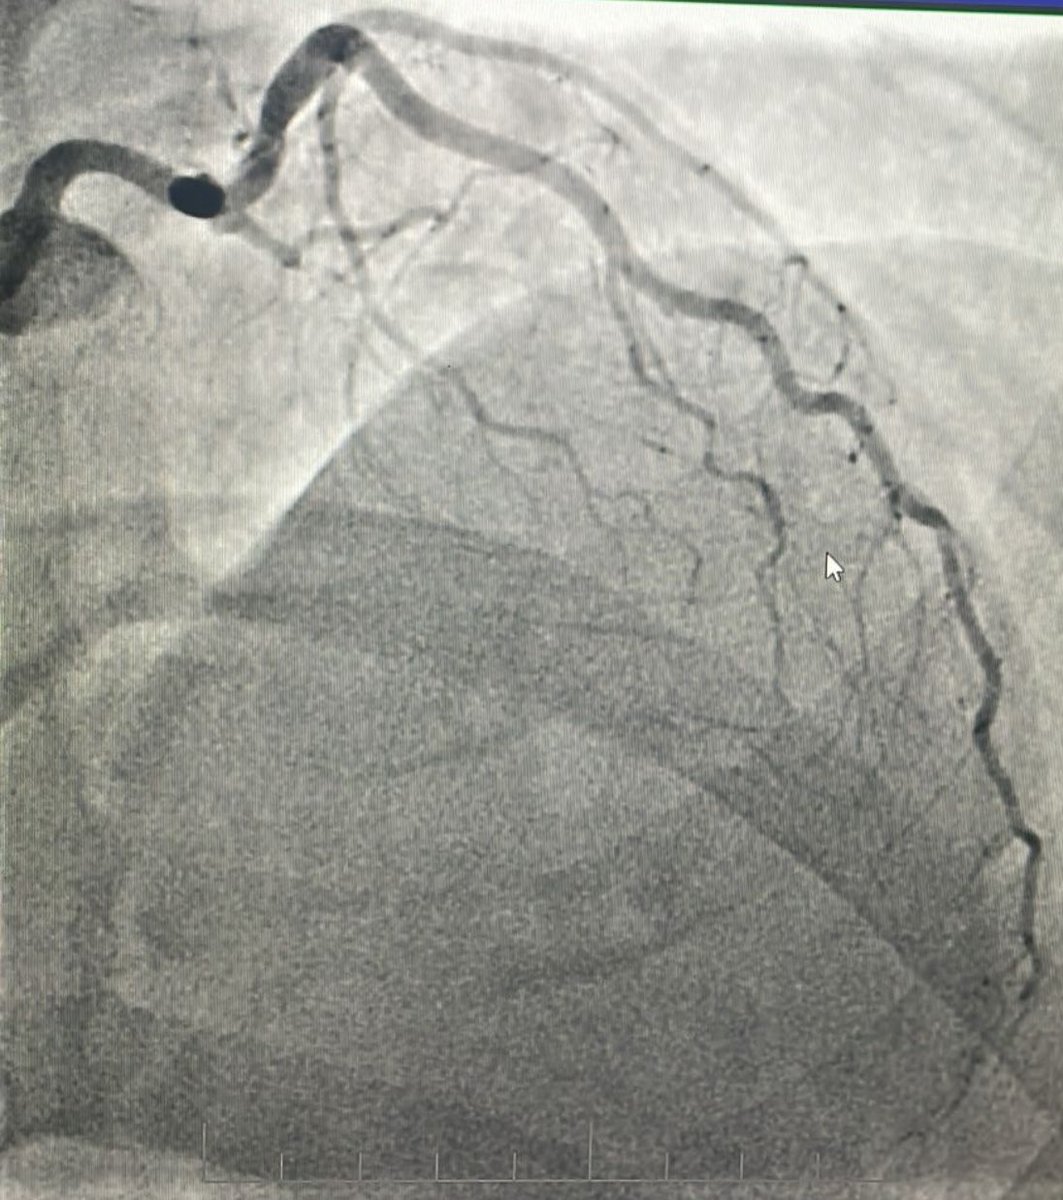

CTO LAD 🔹Dual injection 🔹RCA with wire protection 🔹LAD with microcatheter 🔹Trapping technique to secure the wire 🛑 Always secure the donor first 📍 Microcatheter = Stability + Roadmap ⚠️ Don’t rush the setup, good prep = smoother case 😁 Happier than the patient. #CTO…